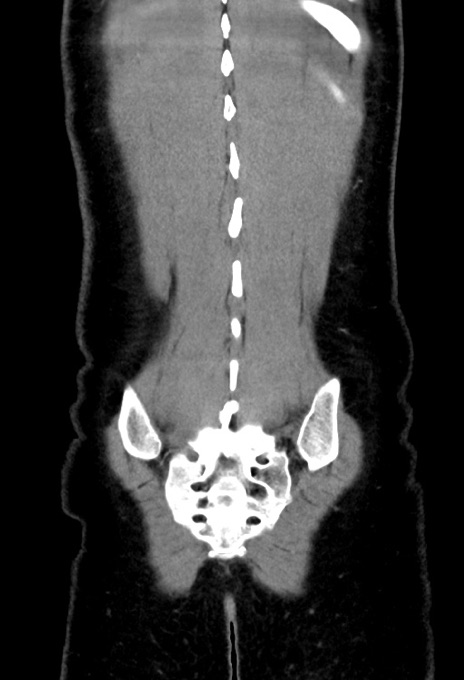

症例17(冠状断像)

【症例】20歳代女性

【主訴】嘔吐、下腹部痛

【現病歴】昨日夕食後に嘔吐し下腹部痛が出現。本日になっても嘔吐持続し改善しないため来院。

【身体所見】意識清明、BT 37.2℃、BP 108/67mmHg、腹部:平坦、やや硬、下腹部正中から右にかけて圧痛あり、反跳痛軽度あり、tapping pain(+)。

【データ】WBC 13600、CRP 14.94